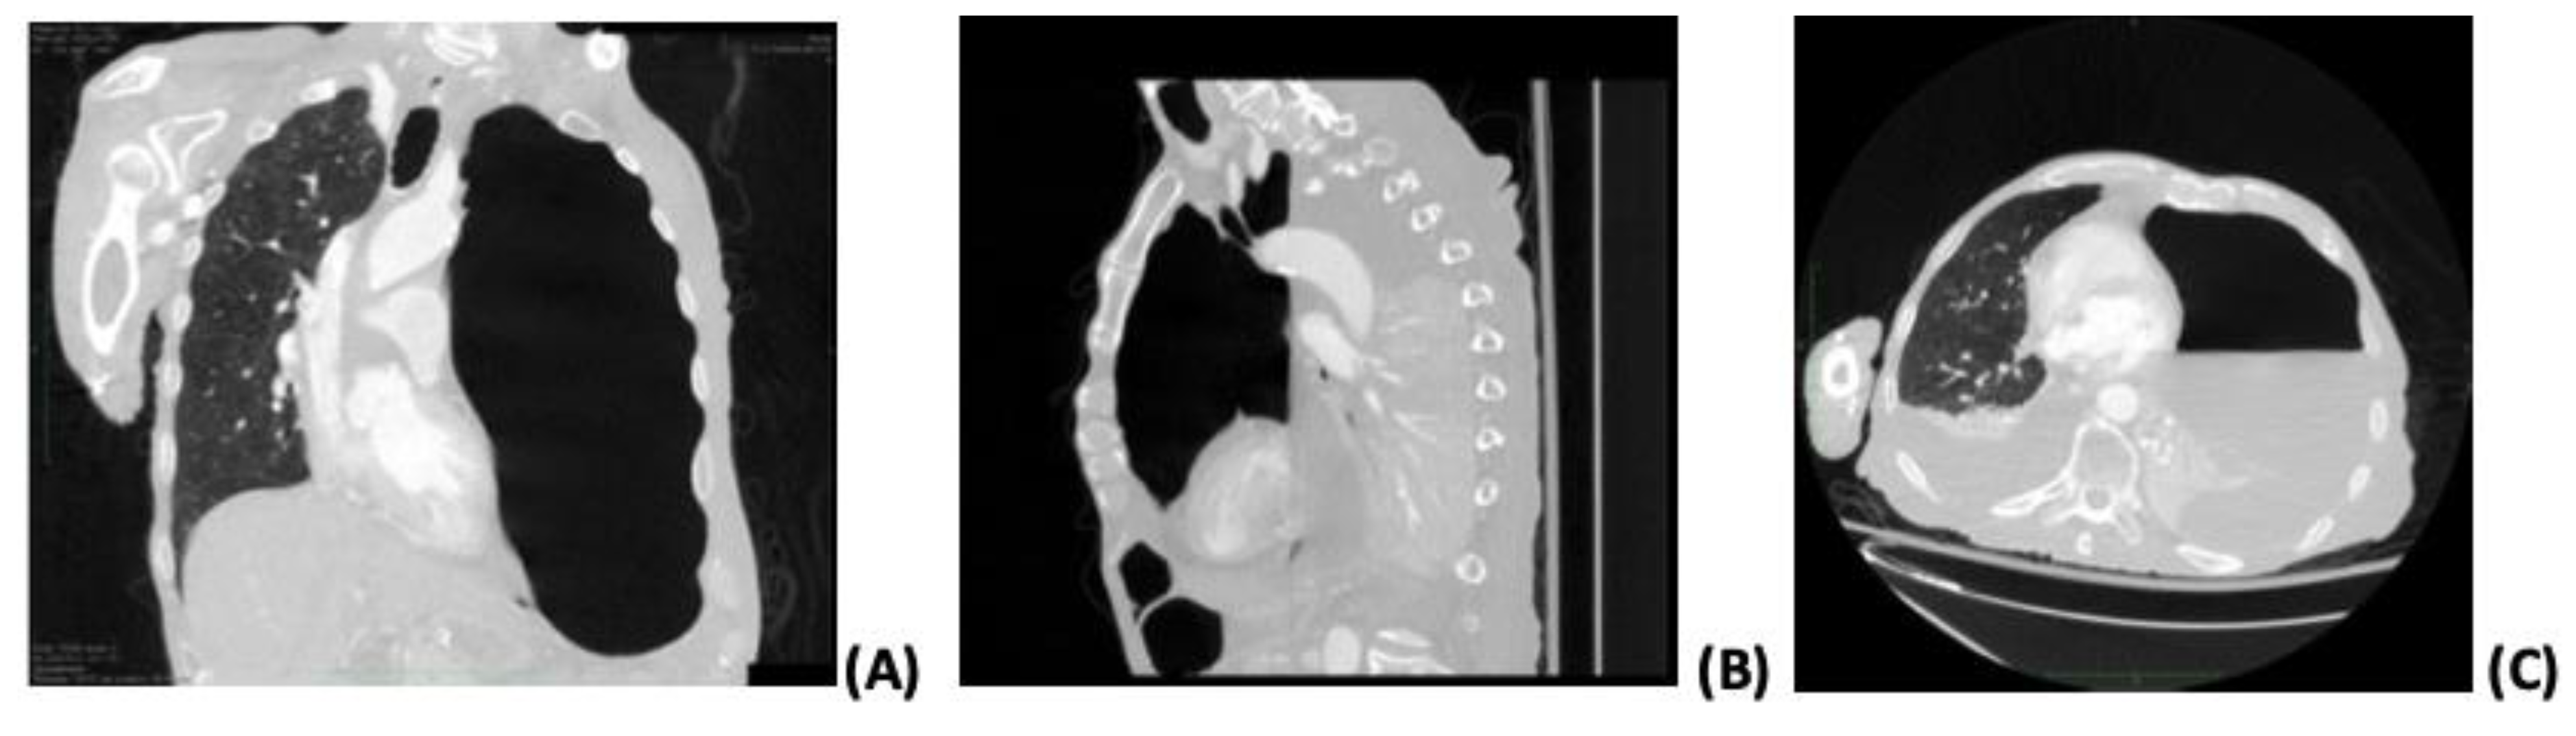

Figure 1.

Computed tomography findings. Coronal (A), sagittal (B), and axial (C) planes show severe volume left-sided hydropneumothorax accompanied by distinct areas of low attenuation with decreased parenchymal enhancement of the upper left lobe, indicating necrotizing pneumonia.